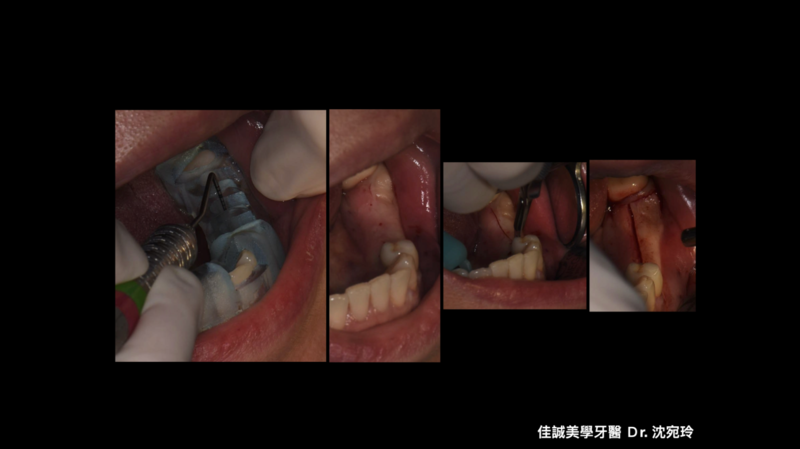

治療的開始是我們幫病患解決了疼痛,從病患腫痛,拆假牙、拔牙,恰好左下第一小臼齒為根管難症,仰賴錢正原醫師的成功顯微根管治療,取的病患的信任。接著我們一步步的重建,也因為這區是長達十幾年的五單位牙橋,拆掉後除了病患明顯左邊不好咀嚼,因此對於重建有強烈的企圖心,另外我們也看到因為長久缺牙而有牙脊萎縮,並伴隨角質化上皮缺損。缺損的骨頭部分我們是補得回來的,但一次三顆植體加上水平補骨,若在缺角質化上皮的這區手術,總覺得風險高了些。因為若有足夠的角質化上皮,可以讓我們植牙手術補骨縫合時,將縫線進針在角質化上皮內,縫線與角質化上皮內就像釘書針扎實的釘錨著,能對抗術後腫脹期防止傷口裂開,讓手術更能保證成功; 另外,若於其後補上骨粉和再生膜後,牙脊上的角質化上皮也相對穩定,不會在咀嚼時移動,讓其下方的骨粉可以好好轉換成自體骨; 角質化上皮的功能不只如上,在將來植體接假牙出來後,在咀嚼時,也因有足夠角質化上皮的包覆,能防止食物掉入和植體相接的牙肉內,防止植體周圍炎的產生。談到植體周圍炎的預防,植體植入的位置,最好平行假牙咬合軸向的受力,並且出孔位置在假牙的正中心。

以這個案例,我們量測了牙脊缺牙區的總寬度,再精算植體間距和植體寬度,後牙區小臼齒種植寬度長度4 mm X 11.5mm的植體,大臼齒則置入兩支寬度長度5 mmX11.5mm的植體,而在設計時在軟體內要讓三顆植體盡可能平行,以利將來植牙贋復製作,減少應力集中造成植體周圍炎的可能。我們利用模子的STL檔和斷層掃描的DICOM檔做疊合,在Bluesky軟體內,由醫師自己設計出最佳的植體位置、寬度長度,再請專業的3D列印公司做數位模板輸出。因為在軟體內我們已經看出將來植體的位置和需補骨的量,進而反推切線的位置,最後我們知道角質化上皮終究都需要補一場,於是治療計畫一開始就是先補上角質化上皮,等四個月後軟組織穩定,我們接著利用手術導板植入三個植體,並於當次補入骨粉和再生膜,術後如我們預期,傷口恢復良好。